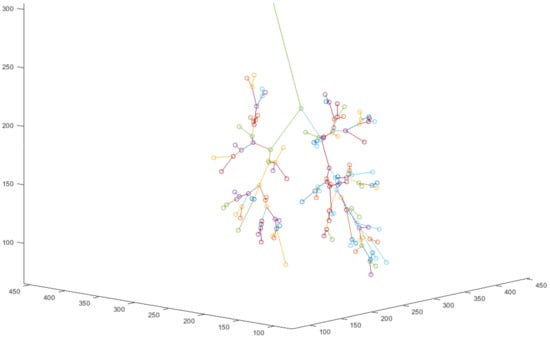

3.4. Data Systematization

The trend information is enough for identifying the bronchus name. To reduce nonrequired information and accelerate identification, the airways should be shaped into a tree using the method in Section 2.4, as shown in Figure 8 and Figure 9.

Figure 8.

Airway skeleton drawing. Here, orange is a node and blue is a line.

Figure 9.

Visual tree structure.